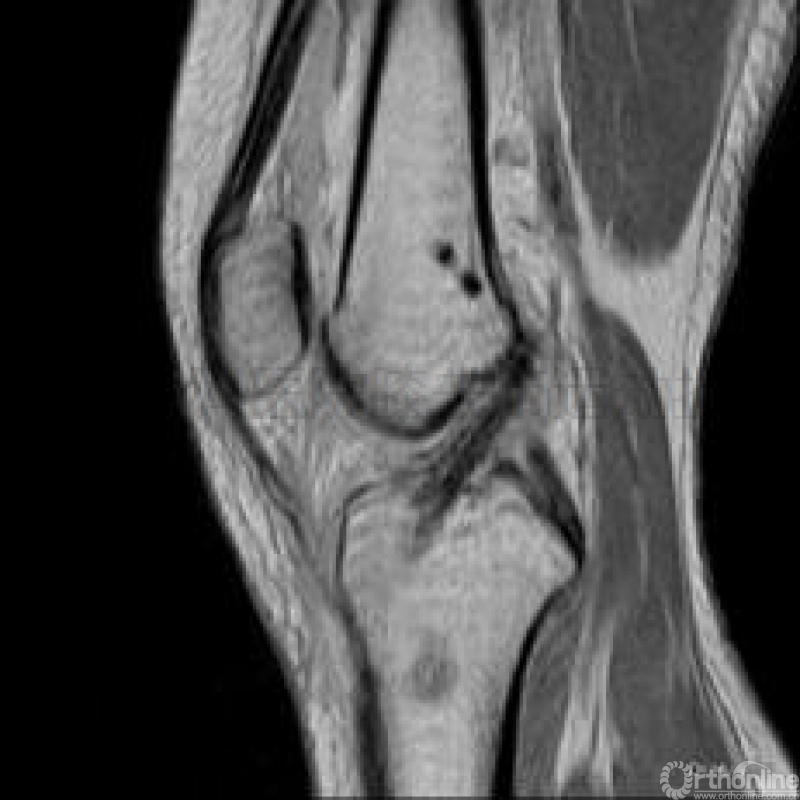

术后复查的核磁共振证实未发生上述医源性损伤(图示十)。

图示十临床使用Sunbird完成手术后之核磁共振检查显示,RigidFix双横穿钉通过术中外髁防穿透式测量,均未穿透外髁骨皮质,无医源性损伤发生。